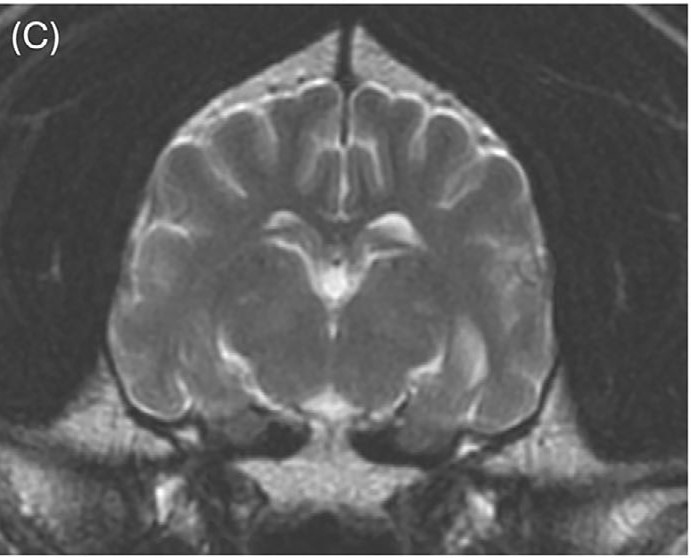

颈椎MRI图像大多未见异常,仅显示颈椎间盘纤维环的轻度非压迫性突出。脑部成像显示双侧对称、边界不清的T2和T2-FLAIR高信号,影响丘脑(图1A)、内侧和外侧膝状体(图2A)、导水管周围灰质和红核(图2A)。在双侧豆状核(图3A)、丘脑(图1B)和膝状核(图2B)内可见T1高信号。这些病变未显示对比增强。未在任何可见的骨或软组织结构中发现异常。

图2.(A)内侧和外侧膝状体区域(白色圆圈)及红核区域(白色箭头)可见双侧对称、边界不清的T2高信号;(B)内侧和外侧膝状体区域(白色圆圈)可见双侧对称、边界不清的T1高信号。

与治疗前相比,先前注意到的T2和T2-FLAIR高信号区域都有显著改善。在丘脑(图4C)、内侧和外侧膝状体以及红核中仅见非常轻微的双侧对称、边界不清的T2高信号(图5C)。先前注意到的豆状核中的T1高信号区域已完全消失(图6B)。

图5.(C)铜螯合治疗开始7个月后,内侧和外侧膝状体区域及红核区域的T2高信号明显改善。